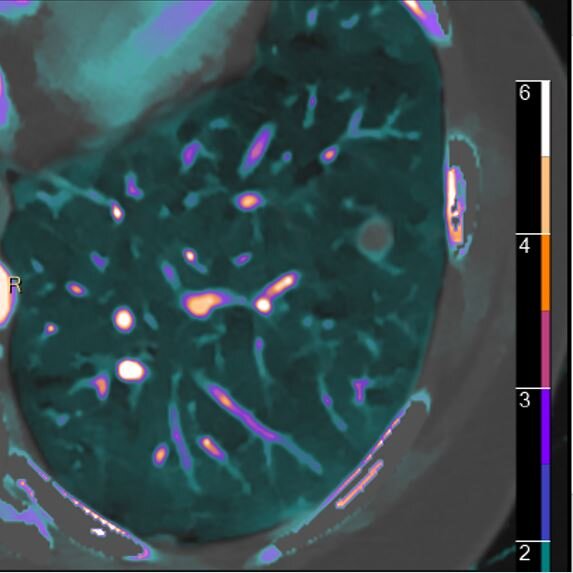

Lung nodule: Spectral and volumetric.